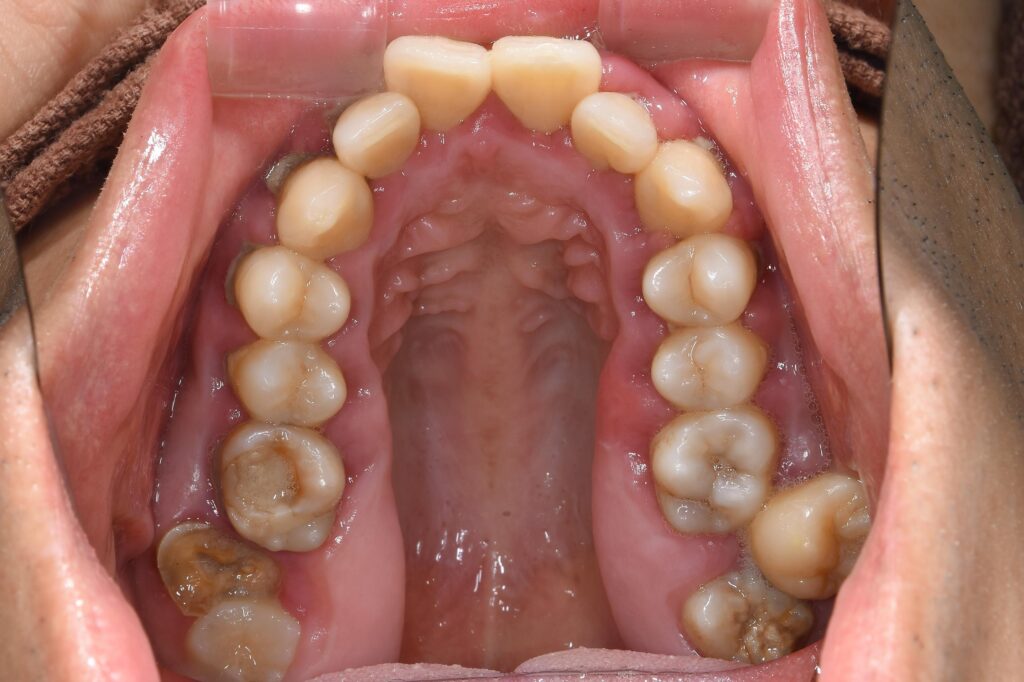

まずは初診時の状態です。

【初診時】

初診時、歯周病・虫歯も進行しており、まずは初期治療として歯周病治療・虫歯治療を行いました。

②虫歯治療・保存が困難な歯牙、親知らずの抜歯処置を行いました。

③歯並びに関して、問題点は歯列弓の狭窄を認め、歯がガタガタになってしまっています。また、上顎の歯が突出してしまい、出っ歯になっています。